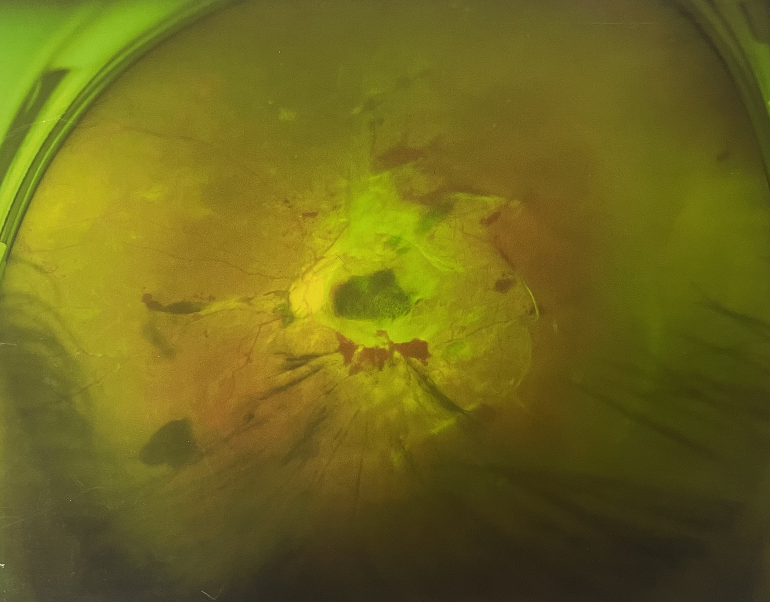

眼底出血一般多久能好?眼底出血可以由眼科本身疾病引起,常見(jiàn)的是視網(wǎng)膜靜脈阻塞、糖尿病視網(wǎng)膜病變、中心性滲出性視網(wǎng)膜病變、視網(wǎng)膜動(dòng)脈硬化、老年性黃斑病變、視網(wǎng)膜靜脈周?chē)住?/div>

另外,眼底出血還可以由全身疾病引起,比如糖尿病可以引起眼底出血,高血壓也會(huì)引起眼底出血,還有嚴(yán)重的腎病,血液方面的疾病都可以導(dǎo)致眼底出血。

眼底出血一般多久能好?眼底出血如果是輕癥,時(shí)間較短的患者大約3-6個(gè)月可以恢復(fù),如果是重癥或者病程較長(zhǎng)的患者,可能要持續(xù)1年,甚至2年時(shí)間。

眼底出血一般多久能好?眼底出血是醫(yī)生用檢眼鏡才能看到,患者和其他人看不見(jiàn)。眼底出血不是單獨(dú)的病,一般來(lái)說(shuō)是由眼科本身疾病造成,還可以由全身疾病造成。比如常見(jiàn)的視網(wǎng)膜靜脈阻塞、糖尿病視網(wǎng)膜病變等引起的眼底出血較常見(jiàn)。眼底出血一般多久能好?所以眼底出血的出血吸收時(shí)間也不一樣,要根據(jù)病情輕重決定其預(yù)后,出血吸收時(shí)間也不一樣。